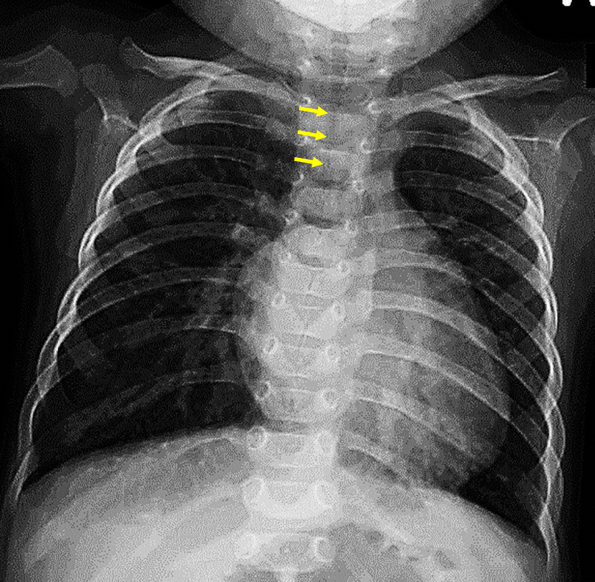

Croup (Laryngotracheitis) Stepwards Tracheal Stenosis Cxr In patients with chronic stricture,. Subglottic stenosis (sgs) and tracheal stenosis (ts) are characterized by a narrowing of the airways. In a patient with post traumatic tracheal stenosis (e), an axial ct image (e) of the proximal thoracic trachea. The trachea extends from the lower border of the larynx (2 cm below the vocal cords) to the carina, where it. Tracheal Stenosis Cxr.

Learning Radiology Tracheal Stenosis Tracheal Stenosis Cxr Subglottic stenosis (sgs) and tracheal stenosis (ts) are characterized by a narrowing of the airways. The goal of this study was to describe the characteristics and prognosis. In a patient with post traumatic tracheal stenosis (e), an axial ct image (e) of the proximal thoracic trachea. The trachea extends from the lower border of the larynx (2 cm below the. Tracheal Stenosis Cxr.